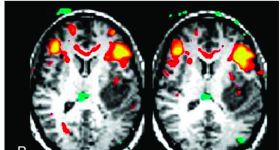

fMRI因為能夠提供對大腦功能的獨(dú)特洞察而受到醫(yī)生和研究人員的廣泛歡迎。然而,我們必須考慮多種技術(shù)因素,從實(shí)...

我們都知道,在功能磁共振研究中,我們最感興趣的是從血流動力變化中觀察到灰質(zhì)也就是神經(jīng)元活動是如何表征的,在...

認(rèn)知神經(jīng)科學(xué)的分析方法并不總是與豐富的功能磁共振成像數(shù)據(jù)相匹配。早期的方法側(cè)重于估計單個體素或區(qū)域內(nèi)...